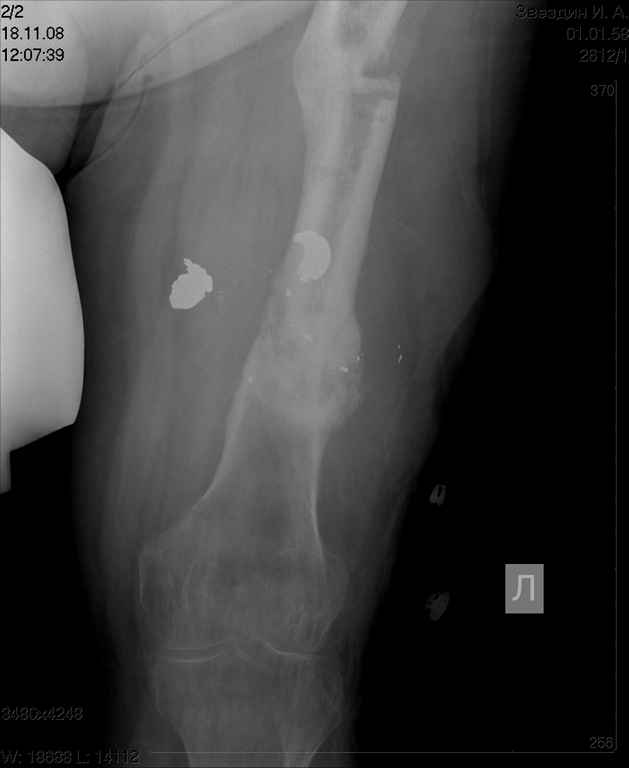

[Ortho] ложный сустав бедра

посылаю снимки отдельно

Имя     : Звездин 2.jpg